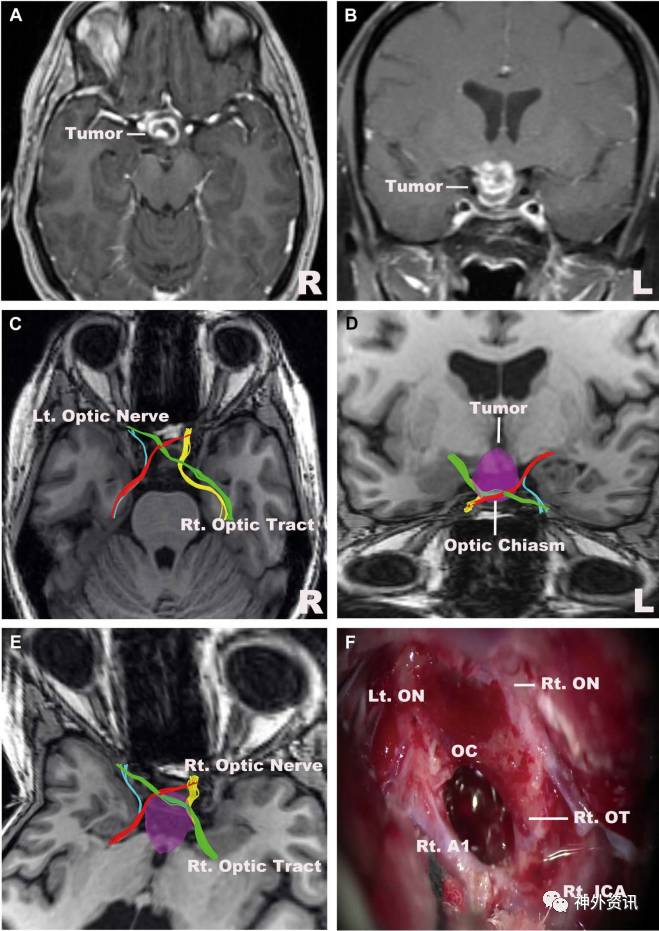

图10. 下丘脑胶质瘤。A. MRI轴向位;B. MRI冠状位;C.视神经、视交叉和视束;D.视交叉和肿瘤的位置关系(正面观);E.右侧眶上入路模拟图;F.术中图像显示,神经纤维束重建图与术中所见一致。A1:大脑前动脉水平部;ICA:颈内动脉。